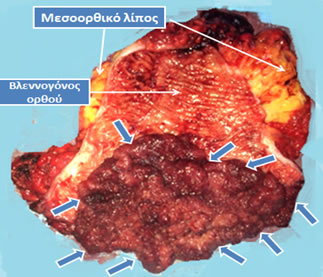

Εικόνα 2.

Επιμήκως διανοιγμένο παρασκεύασμα πολύ χαμηλής πρόσθιας εκτομής (ολικής αφαίρεσης ορθού) για την αντιμετώπιση ευμεγέθους λαχνωτού αδενώματος (μπλε βέλη), που παρουσίαζε υψηλόβαθμη δυσπλασία χωρίς κακοήθεια. Ο ασθενής εμφανίστηκε με εκκριτικού τύπου διάρροιες, αφυδάτωση και υποκαλιαιμία, που συχνά προκαλούνται από μεγάλα αδενώματα του ορθού. Λόγω του μεγέθους του η τοπική εκτομή του δεν ήταν εφικτή και απαιτήθηκε αφαίρεση του ορθού. Ακολούθησε κολο-πρωκτική αναστόμωση για την αποκατάσταση της συνέχειας του τελικού τμήματος του πεπτικού σωλήνα.

(Από το προσωπικό αρχείο του Γ. Θεοδωρόπουλου)